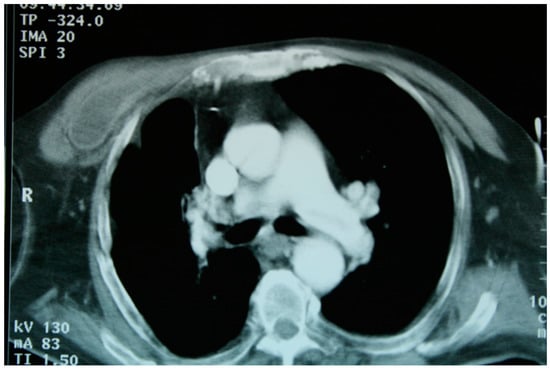

A patient with multiple bilateral lung lesions was diagnosed after investigations for a large hepatic lesion that turned out to be echinococcosis. A 41-year-old male patient reported abdominal pain and shortness of breath and was referred to the hospital by a primary care physician. Primary radiological investigations revealed a large hepatic lesion and multiple bilateral pulmonary lesions. Magnetic resonance imaging (MRI) was performed to evaluate the hepatic lesion (Figure 1), while chest X-rays and computed tomography (CT) were performed prior to admission to the Department of Thoracic Surgery. CT detected two right lower lobe lesions in segment 6 (diameters 4.6 cm, 1.4 cm) and one in segment 8 measuring 1 cm. In the left lower lobe, there was a single 4 cm lesion in segment 9 (Figure 2).

Figure 5. (AF): A chest CT of patient 1 showing ruptured continuity of the hepatic lesion. The right lower lobe bronchi are filled with fluid from hepatic lesion. At bronchoscopy, an S10 fistula was detected.